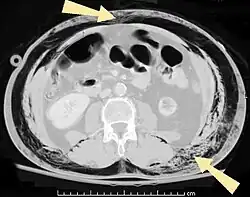

O enfisema pode produzir protuberâncias, como nódulos móveis com ruídos crepitantes a palpação. Em uma radiografia de tórax, o enfisema subcutâneo pode ser visto como estriações radioluzentes (escuras) nas áreas com músculos. O ar nos tecidos subcutâneos pode interferir na radiografia do tórax, potencialmente obscurecendo condições graves, como o pneumotórax. Também pode reduzir a eficácia do ultrassom.[8] Também é visível na tomografia e na ressonância magnética como bolhas escuras.